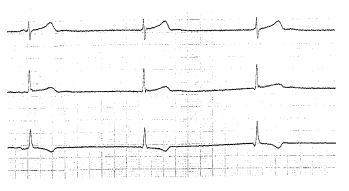

La práctica de deportes de alto rendimiento produce adaptaciones en el aparato cardiovascular que se manifiestan a través de diversos cambios clínicos electrocardiográficos y ecocardiográficos, los cuales se detectan en el examen del atleta. El cardiólogo del deporte está cumpliendo una función muy importante, no sólo en el control del deportista con cardiopatía, sino en las evaluaciones de salud y aptitud para el deporte. Su inserción en la preparación del atleta ha permitido que se cuente con un profesional capacitado en la comprensión de los distintos procesos involucrados en el entrenamiento y los estímulos necesarios para maximizar el rendimiento en las diferentes áreas metabólicas. Los cambios en el corazón del deportista se manifiestan como resultado de modificaciones morfológicas, funcionales y en el sistema nervioso autónomo. El electrocardiograma puede presentar trastornos del ritmo, de la conducción auriculoventricular e intraauricular y ventricular, aumentos de voltaje del QRS y alteraciones diversas de la repolarización ventricular. Los cambios morfológicos detectados por ecocardiografía por lo general no son muy manifiestos y están relacionados con aumentos en las dimensiones cavitarias y en los espesores parietales. La presentación de hallazgos clínicos, eléctricos y ecocardiográficos en el examen del atleta puede llevar a confusiones diagnósticas con cuadros patológicos. La falta de uniformidad de estos cambios en atletas de igual grupo etario y con niveles similares de entrenamiento induce a pensar en factores genéticos involucrados en su aparición. En el presente artículo de revisión se presentan los hallazgos más frecuentes en el examen cardiológico del atleta, su prevalencia y significación clínica.